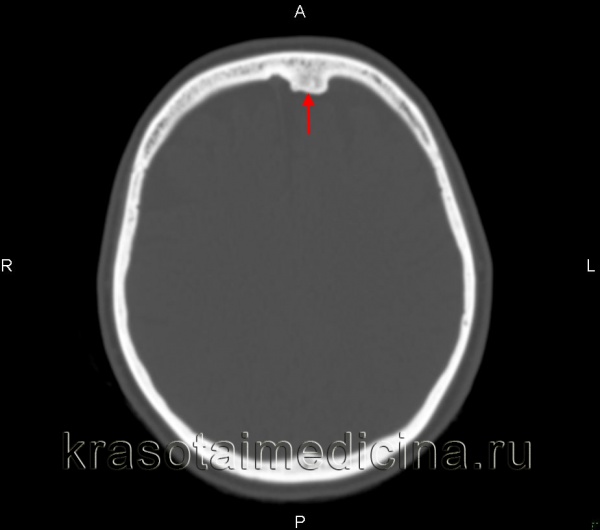

(Справа) На аксиальной КТ в костном окне определяется плотная компактная остеома правой лобной пазухи, пересекающая срединную линию, рас пространяющаяся влево и интракраниальною обеих лобных пазухах присутствует «запертый» секрет. Остеомы чаще обнаруживаются в лобных пазухах, чем в любых других. (Слева) На аксиальной КЛКТ определяется губчатая остеома передней стенки правой верхнечелюстной пазухи. Остеома состоит из ядра, представленного губчатой костью, покрытого толстой и ровной кортикальной пластинкой.

В связи с частым бессимптомным течением и неспецифической симптоматикой заболевания количество случайно диагностированных остеом при компьютерной томографии (КТ) носа и околоносовых пазух достигает 1-3% [3, 31]. На К.Т. опухоль обычно представлена плотной гомогенной массой с резкими, отчетливыми контурами [1, 22]. В связи с тем, что очертания опухоли совпадают с контуром пазухи, не всегда удается установить точку прикрепления новообразования («ножку») к стенке синуса [11]. Точно определить анатомическую локализацию образования позволяет однофотонная эмиссионная КТ, благодаря накоплению 99m Tc-метилендифосфоната [32]. Отмечаются также преимущества магнитно-резонансной томографии при интракраниальном росте новообразования [33].